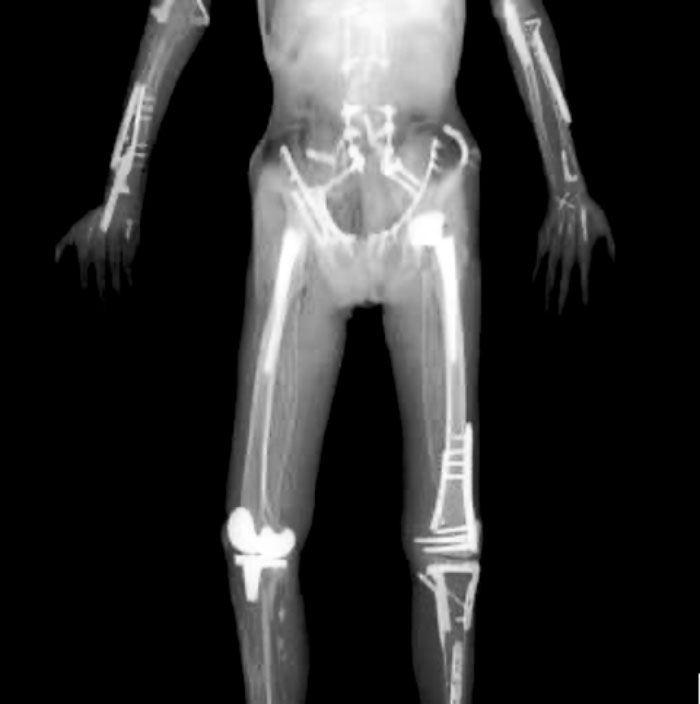

En la foto se muestra una imagen obtenida por rayos X del piloto Travis Pastrana. En ella se pueden ver los pins, injertos óseos, varillas metálicas, clavos etc. que le han ido colocando progresivamente a lo largo de su carrera deportiva. Y sí, efectivamente todos esos “remiendos” le han permitido mantener su actividad corporal biomecánica, ¿pero a qué coste?. Evidentemente cuando dejó de ser rentable ya no se le practicaron más inserciones protésicas y los traumas sufridos a buen seguro le pasarán una enorme factura en su calidad de vida, además de una pérdida funcional.